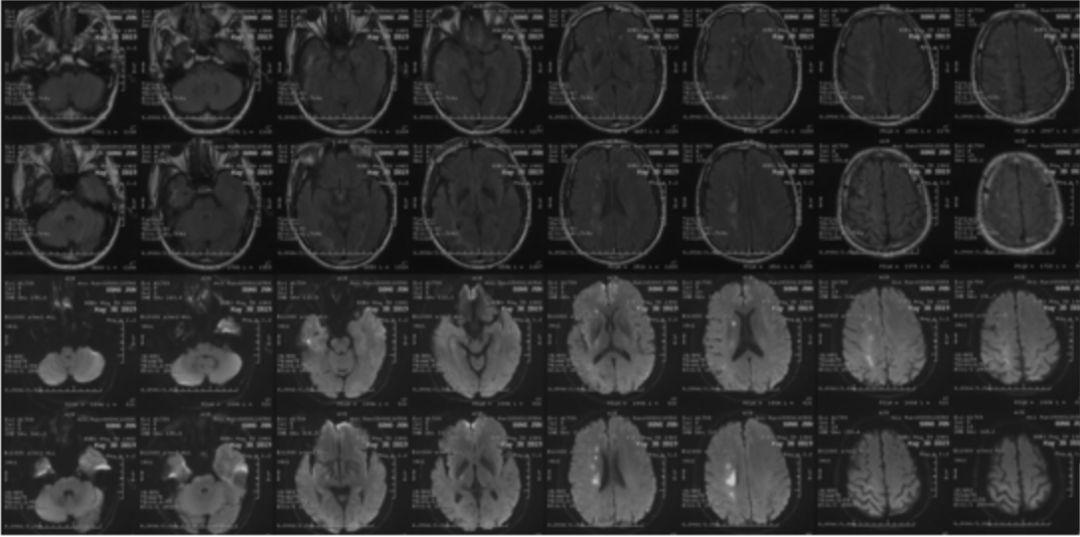

2019-05-24外院头颅MRI+MRA+DWI:右侧基底节区、放射冠、半卵圆中心脑梗死,右侧颈内动脉闭塞(图1)。

图1